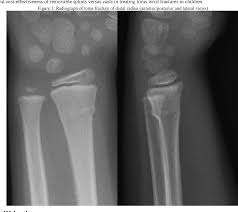

Radiograph Of Torus Fracture Of Distal Radius Anterior Posterior And Download Scientific Diagram

Radiograph Of Torus Fracture Of Distal Radius Anterior Posterior And Download Scientific Diagram from www.researchgate.net